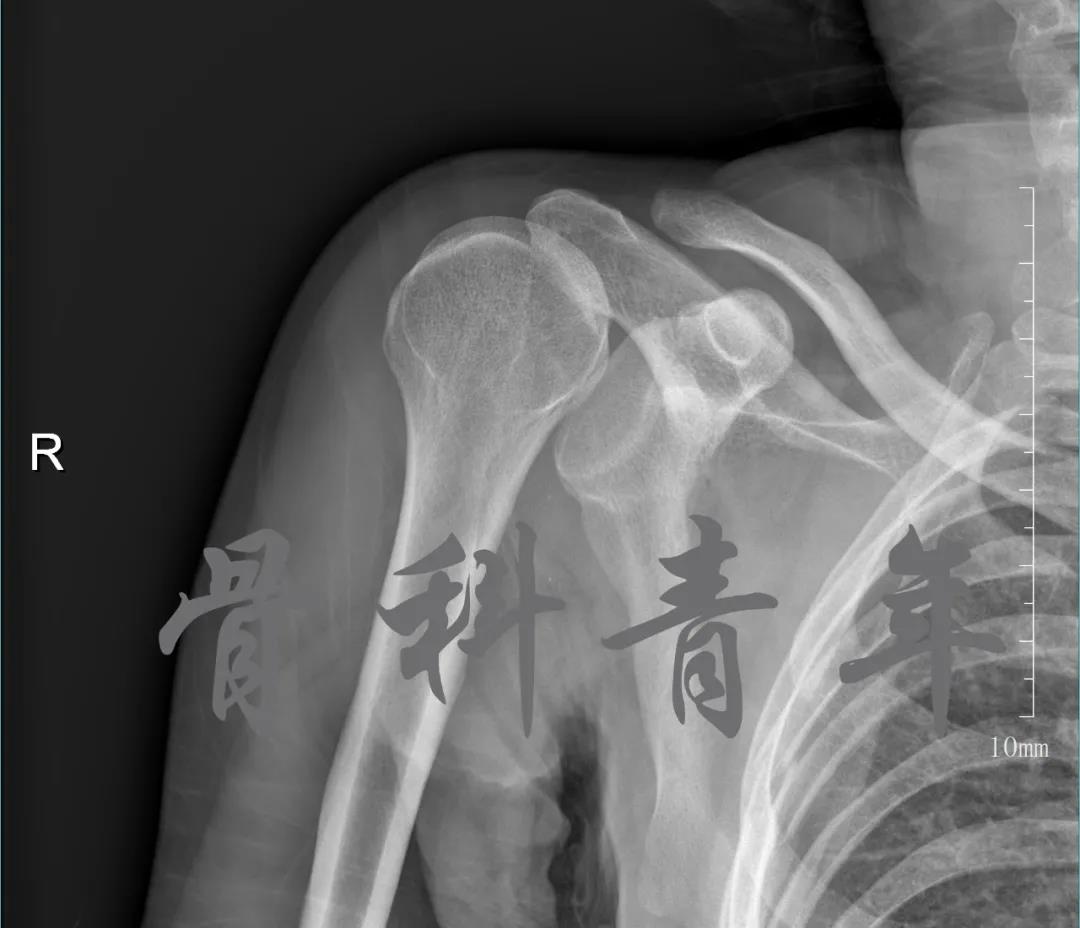

简要病史:骑摩托车跌倒致左肩部肿痛,活动受限,就诊于当地医院,拍片及磁共振检查后诊断为肩袖损伤及肩关节半脱位,予以悬吊固定,因症状缓解不明显就诊于我院。外院拍片情况如下:

应该说是一个典型的“灯泡征”影像,但是并未引起注意。

当地接诊医生应该说还是很负责的,同时拍了健侧片对比: